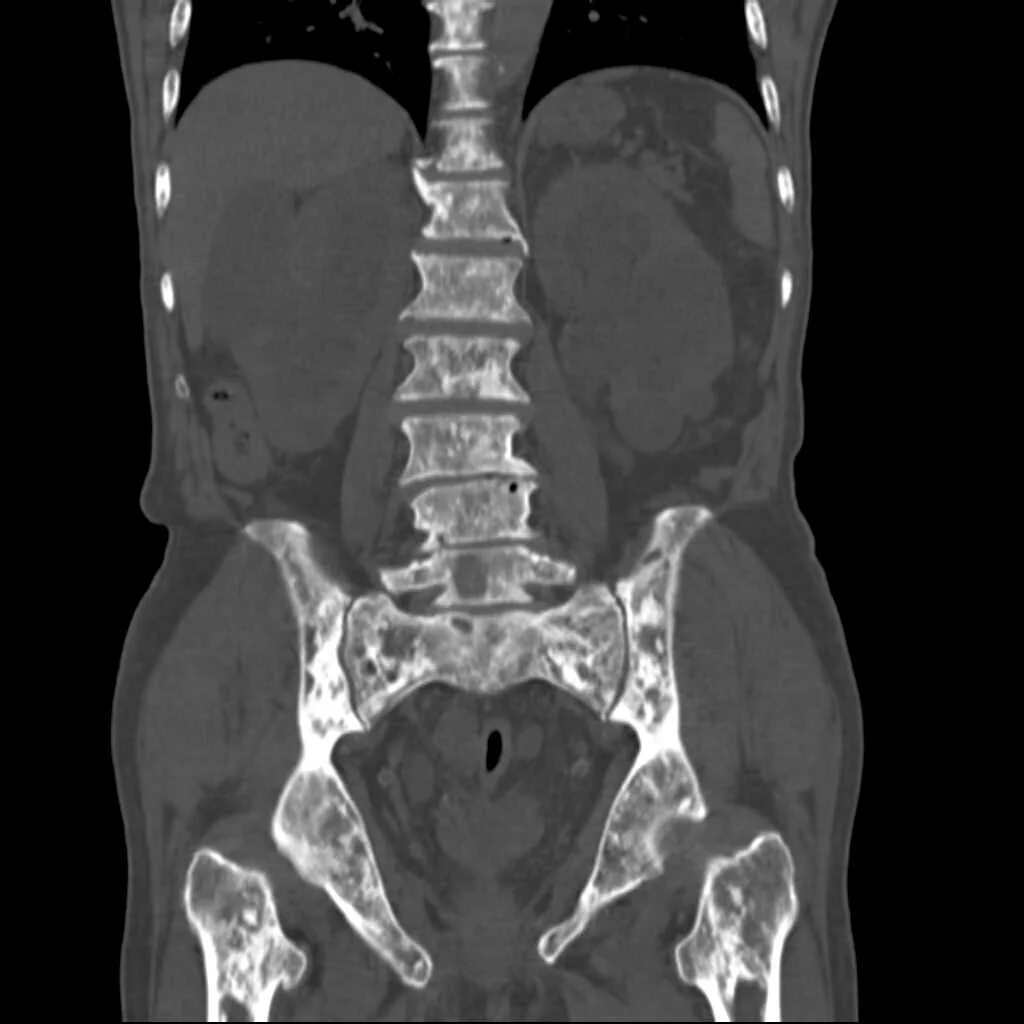

Химиотерапия метастазы кости